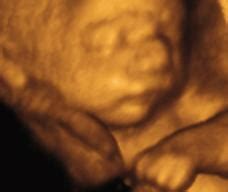

宝宝发育 宝宝的眼睛也将开始发育。现在的胚胎呈现为弯弯的形状,那突出来的肿块就是胎儿的头部。在头部两侧胎儿耳道及内耳将出现的地方可以看见一个小小的窝儿。胎儿在6周时乳牙就开始发育,形成牙胚,恒牙胚在胎儿4~5个月时也开始发育。人的牙齿发育需要很长的时间,但不论乳牙胚还是恒牙胚都是在胎儿期发育的,发育钙化的好坏,与日后牙齿的萌出、乳牙的脱落、牙齿间隙的大小和牙齿的生出与发展均有直接关系。先天不足,钙化不良,不仅牙齿形态可永久性异常,而且抗龋能力也会下降。